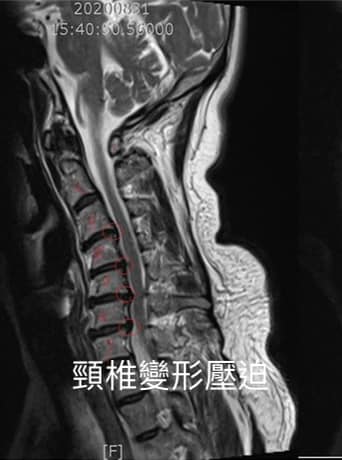

⚠️診斷: 1.頸椎變形反弓

2. C3C4;C4C5;C5C6脊髓型

頸椎病

臨床上很多頸椎病的個案頸椎的正常前凸曲線都已經消失,嚴重者甚至是有反弓的曲線!就如個案竇先生有非常典型的肩頸痠痛之外,也伴隨上肢抽痠麻、頭痛、暈眩、喉嚨有異物感

看了他的X光片就知道他的頸椎嚴重變形,已經到反弓的現象,正常頸椎的前凸生理曲線可以幫助頸椎吸收由下肢行走時傳導至頭部的力道,漂亮的弧線是天然的避震系統,他頸椎已經產生「走山」現象 ,頸椎的關節與椎間盤承受過度的壓力,頸椎周邊的肌肉也會因為曲線的消失,而容易變得緊繃,最終導致椎間盤突出壓迫神經根與脊髓!